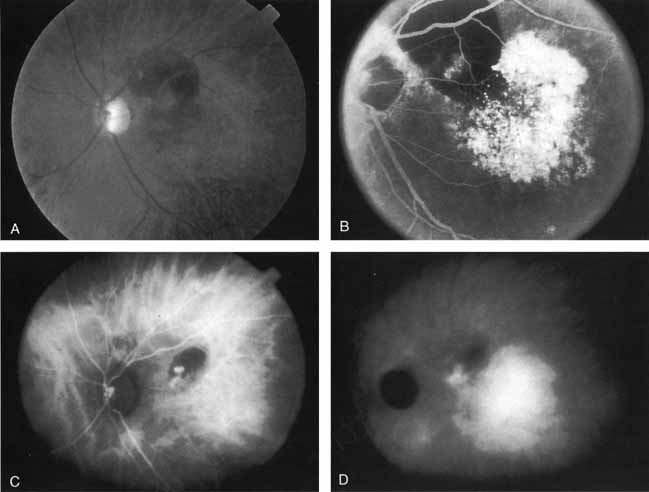

More recently, ICG angiography has begun to play an important role in the management of patients with occult CNV. In particular, the identification and management of two subsets of occult CNV, namely retinal angiomatous proliferation (RAP)34 and polypoidal choroidal neovascularization (PCV),35 are greatly enhanced with ICG angiography. RAP is a distinct subgroup of neovascular AMD in which angiomatous proliferation within the retina is the first manifestation of the process of neovascularization. As the neovascularization proliferates into the outer retina and subretinal space, the angiomatous proliferation is then surrounded by dilated retinal vessels, hemorrhages (preretinal, intraretinal, and subretinal), and exudates. One or more of the related, compensatory retinal vessels perfuse and drain the neovascularization, occasionally forming a retinal–retinal anastomosis (RRA). In these patients, the same indistinct staining seen in occult CNV is present on a fluorescein angiogram. Therefore, most cases of RAP require the use of ICG angiography to make the diagnosis (Fig. 11).34

ICG angiograms of RAP lesions reveal a focal area of intense hyperfluorescence corresponding to a so-called hot-spot of neovascularization with some late extension of the leakage within the retina caused by intraretinal neovascularization (IRN) within the deep layers of the retina. As the IRN progresses down into the subretinal space, the neovascularization present in the choroid joins the IRN to form a large, neovascular complex. At this stage, clinical and angiographic evidence of a vascularized PED (V-PED) is often present. ICG is the preferred method of imaging a V-PED because the serous component of the PED remains hypofluorescent while the vascular component displays hyperfluorescence. ICG angiography may be able to capture direct communication between the retinal and choroidal component of the neovascular complex as they meet to form a retinal choroidal anastomosis (RCA).34 Treatment options of RAP lesions include: traditional laser photocoagulation of the stage 1 and early stage 2 lesions, surgical excision of stage 2 lesions in conjunction with laser diathermy, as well as PDT, alone and in combination with other treatments, particularly triamcinolone acetonide.36,37 Other therapies, both singly and in combination, are currently undergoing investigation for this unique form of neovascular AMD.

Although initially reported exclusively in middle-aged, black females, PCV has since been recognized as a variant of CNV that can be found in all patients with AMD. This entity is characterized by the presence of an inner choroidal vascular network ending in an aneurysmal bulge clinically seen as a red–orange, spheroid, polyp-like structure. Leakage and bleeding from the choroidal vascular abnormalities result in multiple, recurrent, serosanguinous RPE detachments.25,39,40,41 ICG can be used to identify and characterize the vascular abnormality with high sensitivity and specificity.19–21,40–59 Early-phase images of the lesions show a distinct network of vessels within the choroid. Patients with juxtapapillary involvement show a radial, arching pattern with an inner network of vascular channels extending and connecting with smaller, spanning branches that are more numerous and increasingly prominent at the edge of the PCV lesion.

Larger choroidal vessels in the PCV lesion begin to fill before retinal vessels but appear to fill at a slower rate than the retinal vessels. The lesion initially appears noticeably hypofluorescent relative to the surrounding, uninvolved choroid, but soon after the network is first visible with ICG angiography, small, hyperfluorescent “polyps” can be seen within the choroid. These polypoidal structures correspond to the red–orange choroidal excrescence seen clinically. They leak slowly into the surrounding hypofluorescent area, creating increasing hyperfluorescence. In the late phases of the ICG angiogram, a uniform washout pattern is seen as the dye disappears from the polypoidal vascular structure; the late-staining characteristic of occult CNV is not seen in PCV. PCV may be localized to the macular area without any peripapillary involvement. It may present as a network of small branching vessels ending in polypoidal dilation best-imaged with ICG angiography. (Fig. 12)